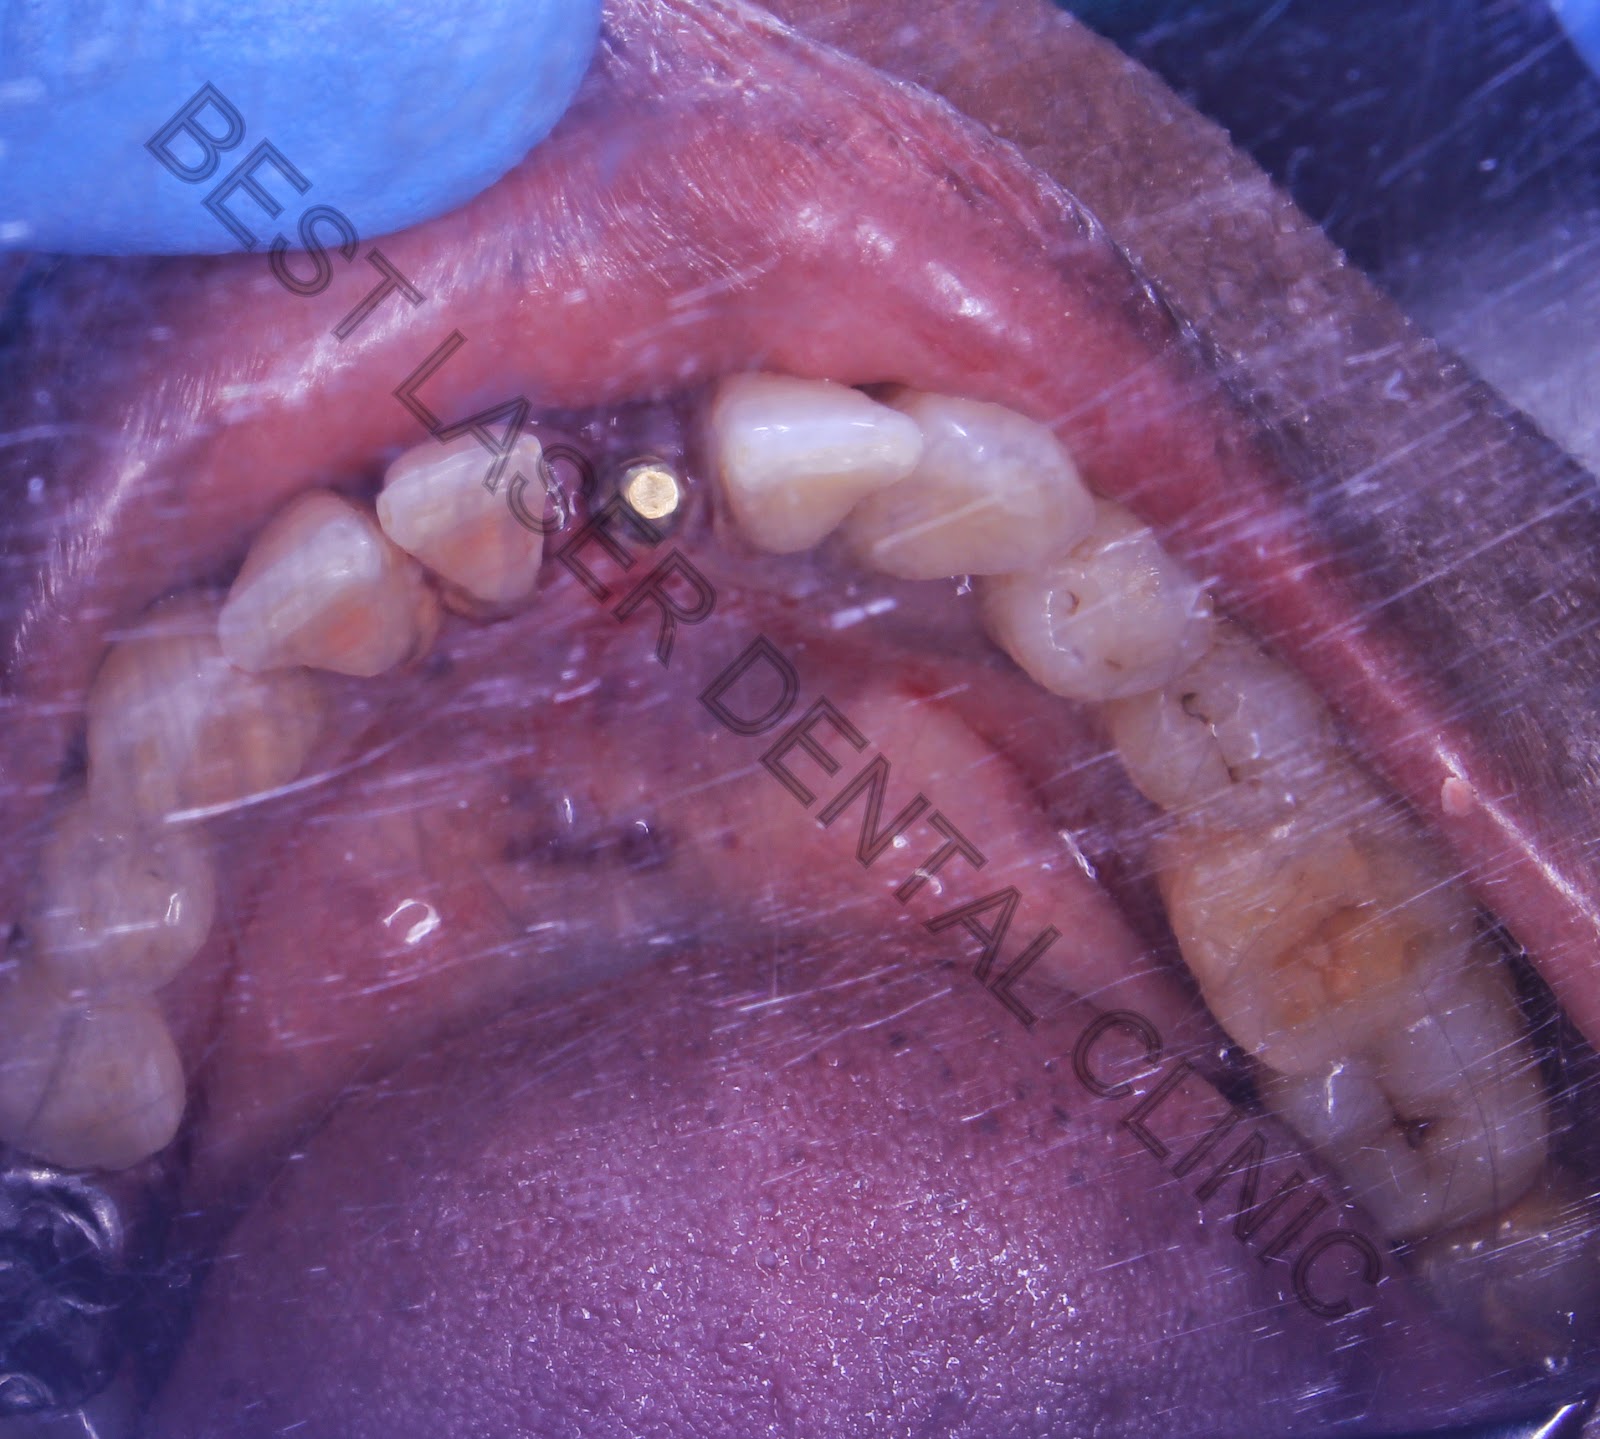

Flapless BCS Single Implant has been placed in the Lower Jaw

Occlusal View of the Lower Jaw of implant Placed in the Teeth